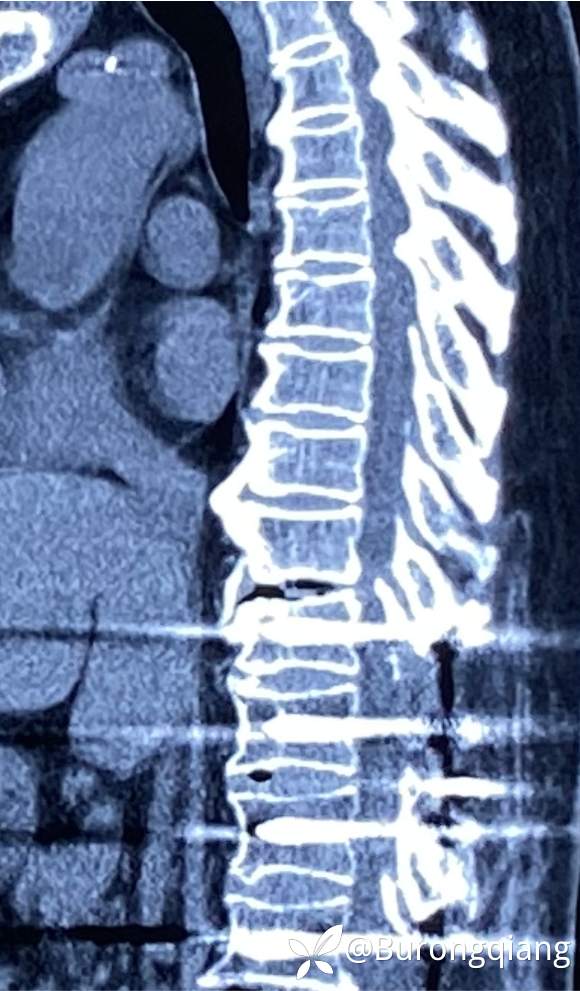

简要病史:患者述2年前无明显诱因出现双下肢大腿憋胀不适症状。外院进一步检查后诊断胸腰椎椎管狭窄,于外院行胸腰椎多节段椎管减压内固定手术治疗,术后症状改善明显,术后10个月再次逐渐出现双下肢麻木无力症状,左侧症状明显,行走时偶有打软腿不适,1年前摔倒致左踝关节骨折,给予内固定手术治疗,术后一直未能下地活动,双下肢麻木无力明显,二便正常。采取保守对症治疗,症状近来逐渐加重。

治疗经过:给予脊柱内镜下椎管扩大减压手术治疗。

术后复查